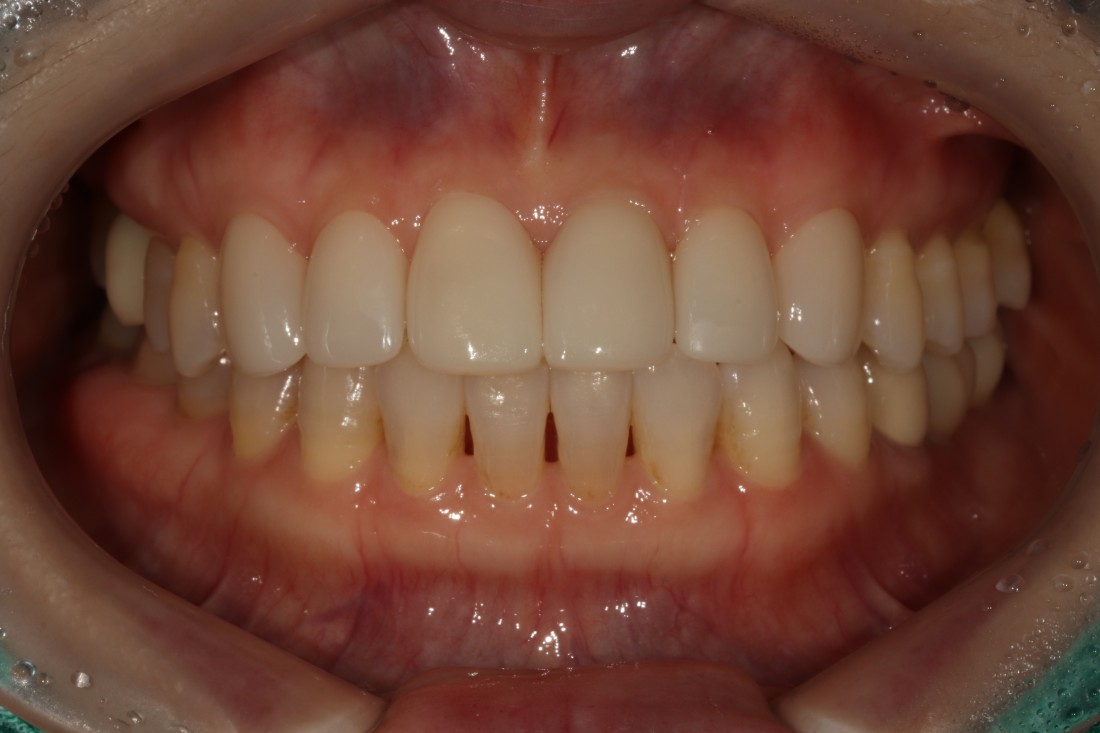

광주 무삭제 라미네이트 치과를 검색하면

정말 많은 치과가 나오는데요.

광고성 글이 아닌

진짜 라미네이트 진료 전/후 사진을

투명하게 공개하는 치과가

가장 신뢰할 수 있으실 겁니다.